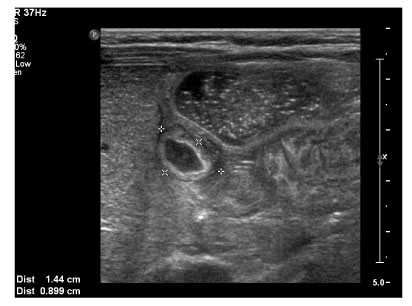

Postnatal ultrasonogram at 4 weeks after birth showing hypoechoic mass (1.4 × 0.9 cm) with thickened wall at the stomach

jkaps-18-35-g002.jpg

Fig. 2 Postnatal ultrasonogram at 4 weeks after birth showing hypoechoic mass (1.4 × 0.9 cm) with thickened wall at the stomach